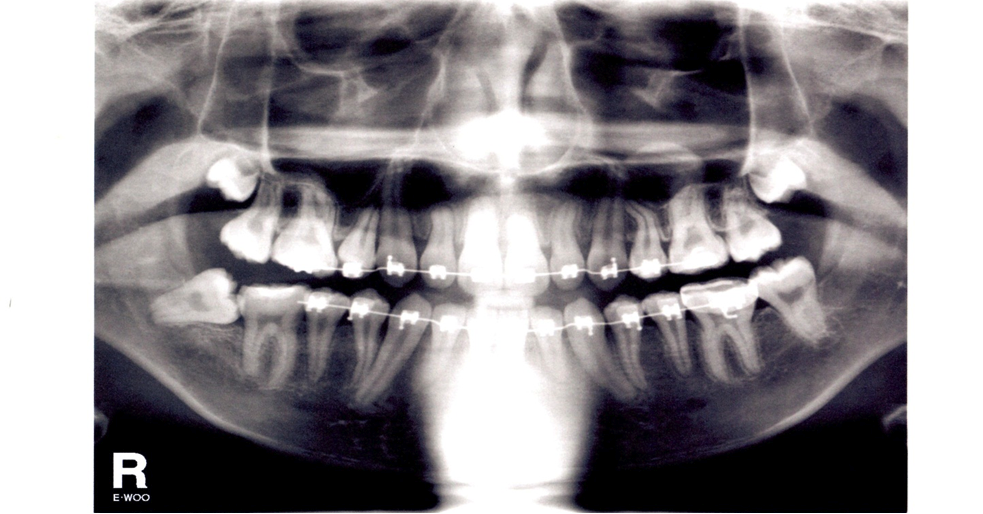

Closeup Xray of Impacted Wisdom Tooth Stock Photo Image of bone What Is Impacted Molar This can lead to a number of oral health problems, including. Impacted wisdom teeth happen when your third molars become partially or fully trapped in your gums or jawbone. A tooth is referred to as ‘ impacted ’ when it fails to fully erupt and remains fully or partially inside the gums. Wisdom teeth are the third set of molars. What Is Impacted Molar.

From www.intechopen.com